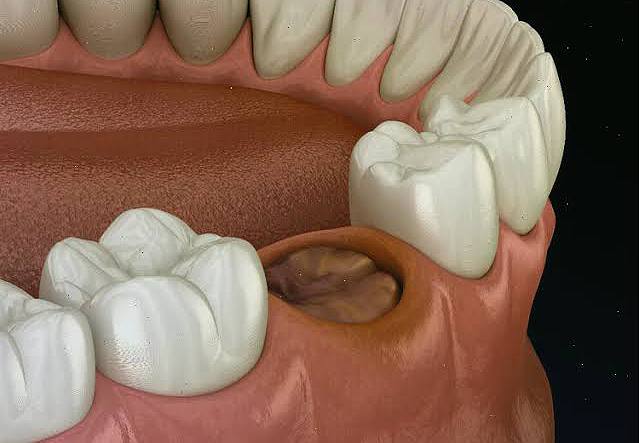

Precision in dentistry is determined not only by the clinician’s experience, but also by the level of visual control over the working field during treatment. Within the clinical approach of